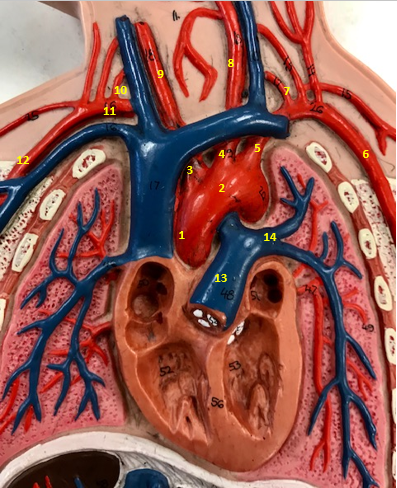

Aorta

Name #2

Brings blood out of left ventricle

Function of aorta

Brachiocephalic artery

Name #3

Supplies oxygenated blood to right arm shoulder neck and head

Function of brachiocephalic artery

Left common carotid artery

Name #4

Supplies oxygenated blood to left neck and head

Function of left common carotid artery

Left subclavian artery

Name #5

Supplies oxygenated blood to left arm shoulder

Function of left subclavian artery

Left axillery artery

Name #6

supplies blood to left armpit and upper limb

Function left axillary artery (6)

Left vertebral artery

Name #7

Supplies blood to brain and spinal cord

Function of left vertebral artery (7)

Left common carotid artery

Name #8

Supplies blood to left neck and head

Function of left common carotid artery (8)

Right common carotid artery

Name #9

Supplies oxygenated blood to right neck and head

Function of right common carotid artery (9)

Right vertebral artery

Name #10

Supplies blood to brain and spinal cord

Function of right vertebral artery (10)

Right subclavian artery

Name #11

Supplies blood to right arm and shoulder

Function of right subclavian artery

Right axillery artery

Name #12

Supplies blood to right armpit and upper limb

Function of right axillery artery (12)

Pulmonary trunk

Name #13

Bring blood out of right ventricle to lungs

Function of pulmonary trunk (13)

Left pulmonary artery

Name #14

Bring blood to left lung

Function of left pulmonary artery (14)